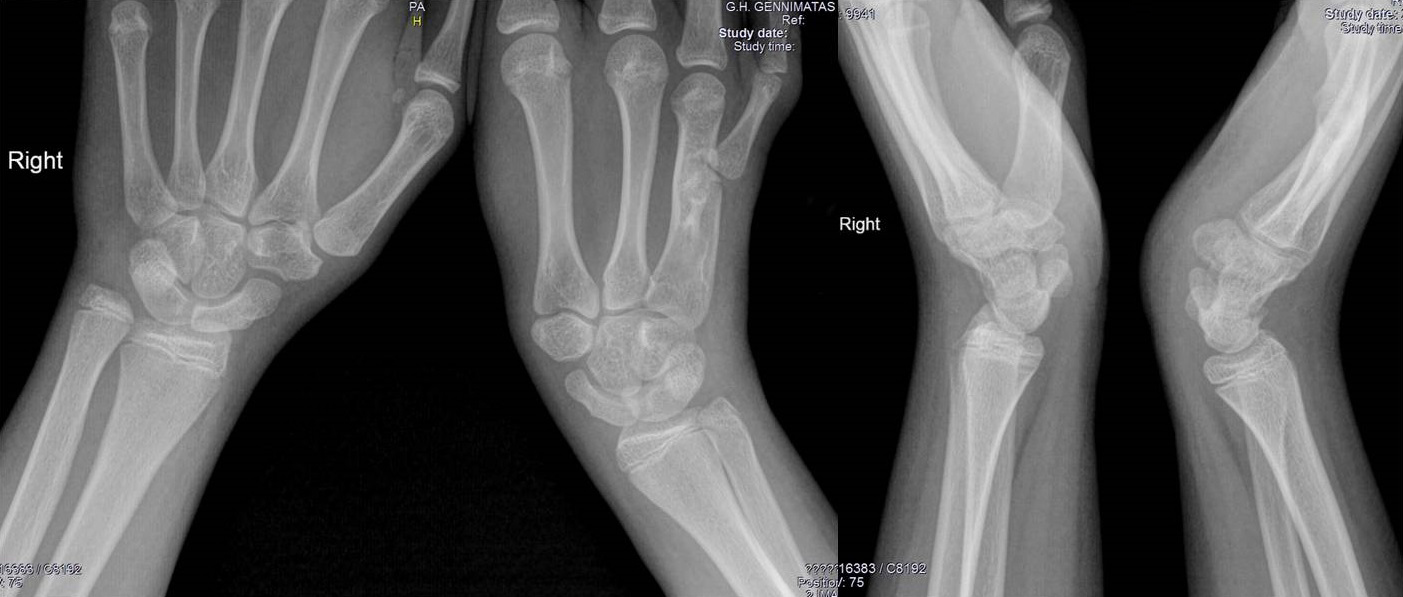

The seventh patient was a 30-year-old woman who presented with right wrist pain after a sports injury. There was no evidence of a fracture line on the radiographs. She had a full recovery after a 3-week protection. The radiographic follow-up evaluation indicated potential negative ulnar variance; a radiograph of both wrists was requested, which showed bilateral scalloping of the distal radius caused by a shortened ulna impinging on the distal radius proximal to the sigmoid notch. A bilateral metacarpal hypoplasia was additionally diagnosed on the radiographs involving the second to fourth metacarpals. She was referred with a diagnosis of bilateral ULD.

Physical and systemic examination, laboratory studies, and tests for autoimmune diseases at our service showed no abnormal findings. There was no radiographic evidence of similar changes in the metatarsals and no evidence of dwarfism or other syndromal disorders in the patient and her family. The radiographic appearance of obliteration of the central metacarpal intramedullary spaces was considered a variant. The final diagnosis was congenital bilateral negative ulnar variance associated with asymptomatic ulnar impingement syndrome (Figure 7).

Figure 7. A 30-year-old woman with bilateral negative ulnar variance associated with asymptomatic ulnar impingement syndrome. Diminished bilateral medullary cavity width is evident in the second to fourth metacarpals.